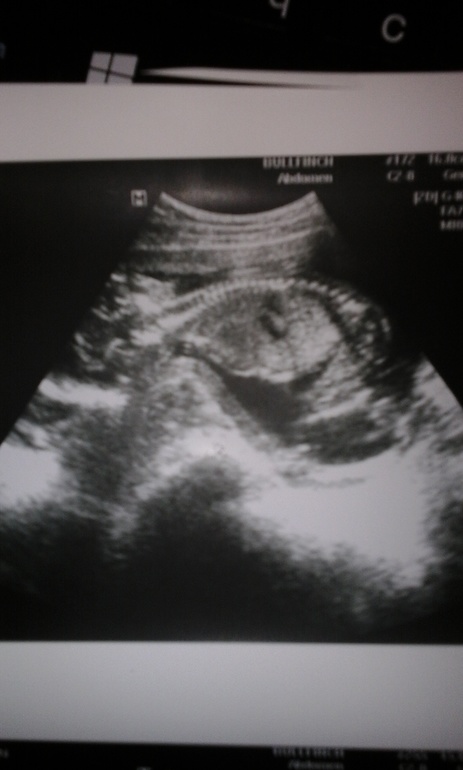

Сынуля)))) ФОТО

Наши будни, наши неделькиНу вот и я дождалась) Сегодня ездила на УЗИ, еще не плановое, но не удержалась, записалась в платную. У нас сынок)) 100 %.

Думаю и комментарии к фото излишни))